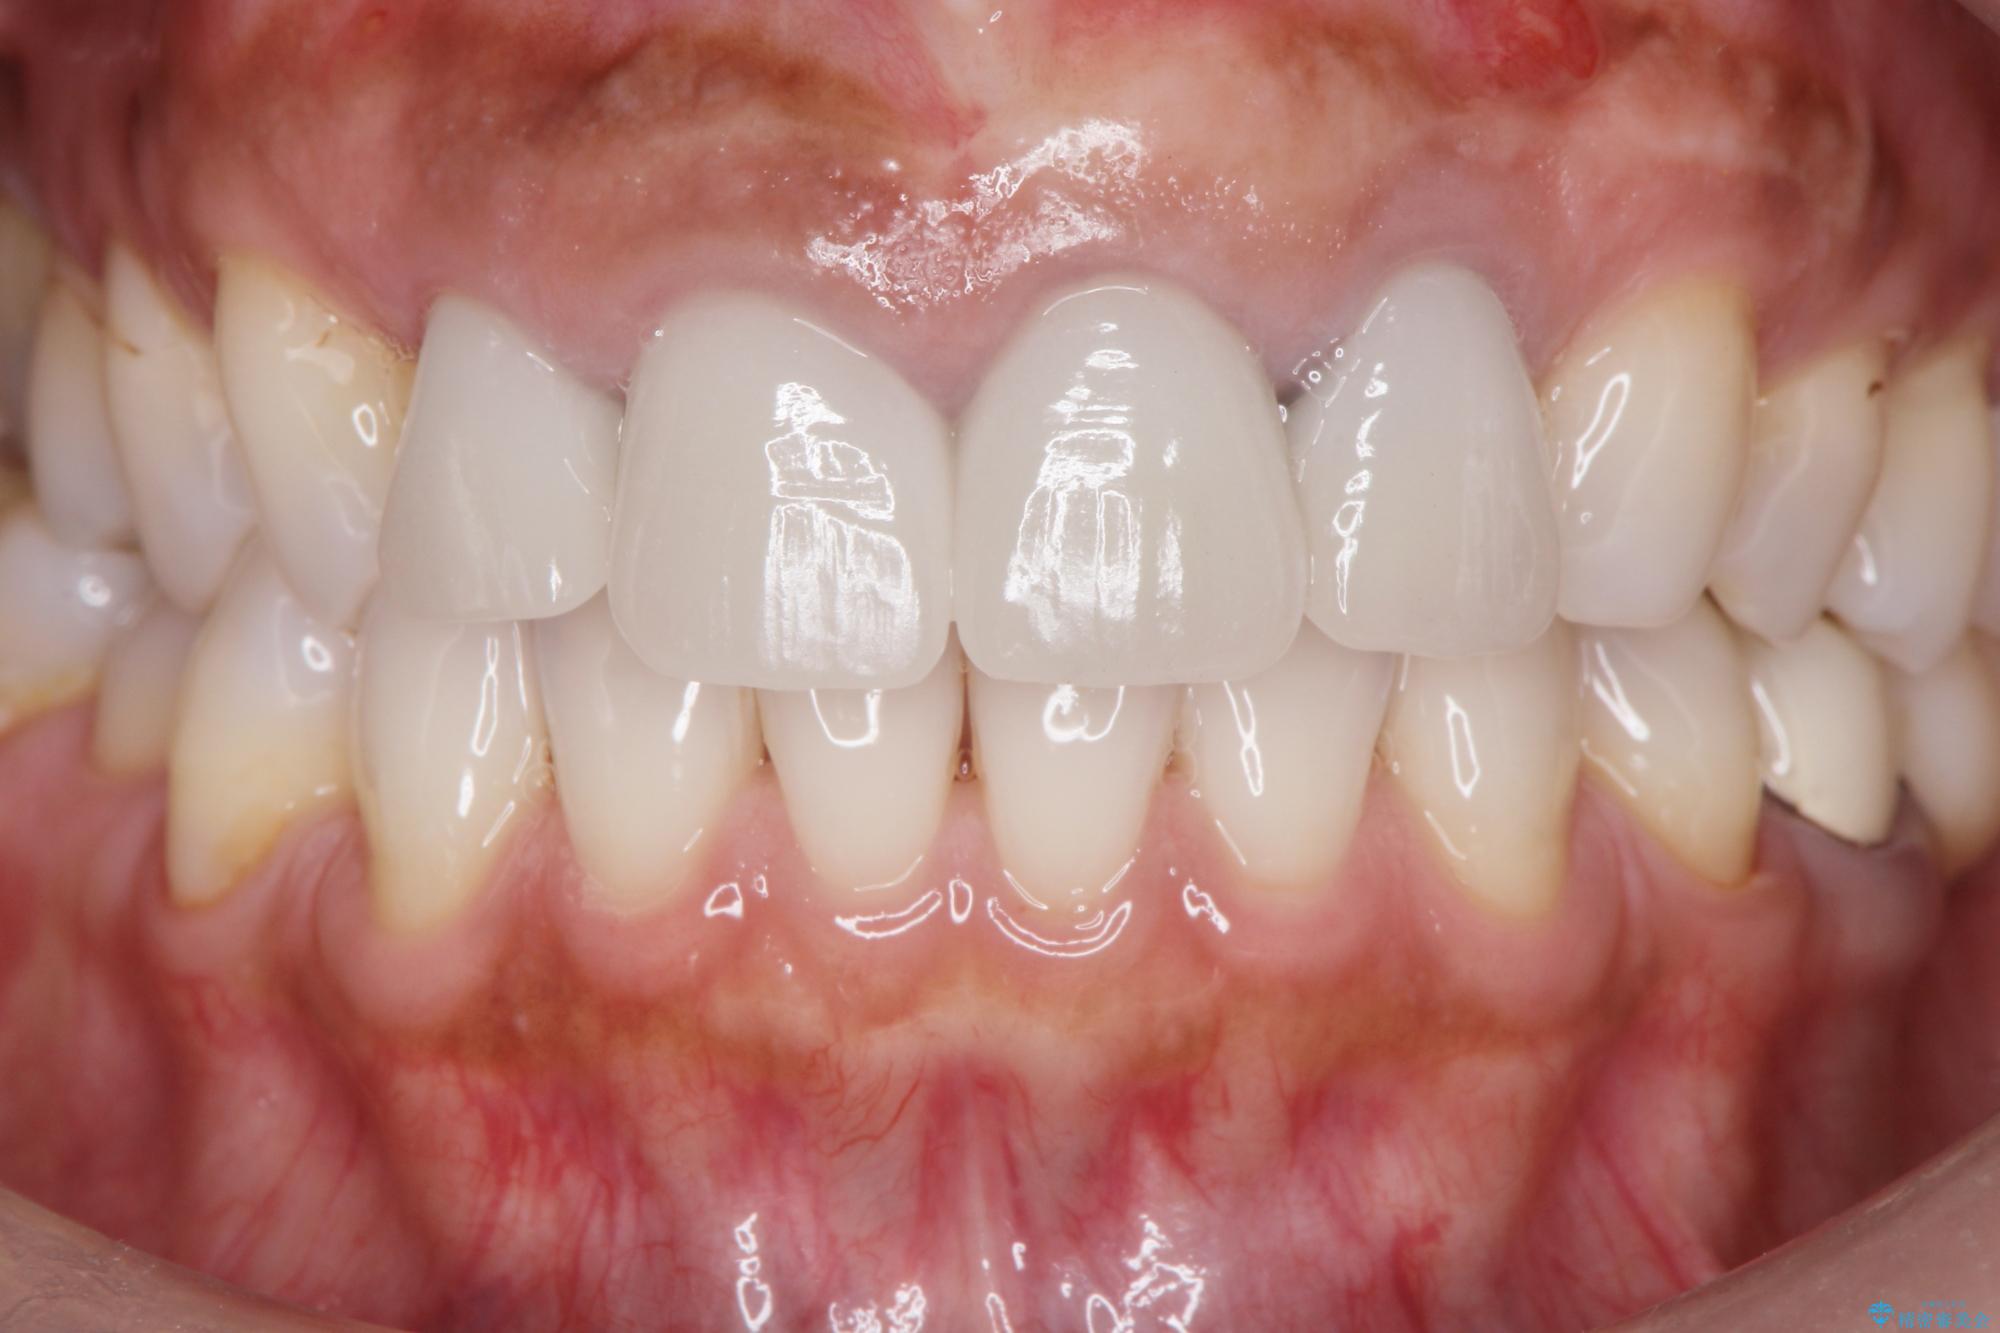

治療前

歯槽堤保存術を併用したブリッジ治療 治療前画像 歯槽堤保存術を併用したブリッジ治療 治療前画像 歯槽堤保存術を併用したブリッジ治療 治療前画像 歯槽堤保存術を併用したブリッジ治療 治療前画像 歯槽堤保存術を併用したブリッジ治療 治療前画像 歯槽堤保存術を併用したブリッジ治療 治療前画像 歯槽堤保存術を併用したブリッジ治療 治療前画像 歯槽堤保存術を併用したブリッジ治療 治療前画像 歯槽堤保存術を併用したブリッジ治療 治療前画像 歯槽堤保存術を併用したブリッジ治療 治療前画像

治療後

歯槽堤保存術を併用したブリッジ治療 治療後画像 歯槽堤保存術を併用したブリッジ治療 治療後画像 歯槽堤保存術を併用したブリッジ治療 治療後画像 歯槽堤保存術を併用したブリッジ治療 治療後画像 歯槽堤保存術を併用したブリッジ治療 治療後画像 歯槽堤保存術を併用したブリッジ治療 治療後画像 歯槽堤保存術を併用したブリッジ治療 治療後画像